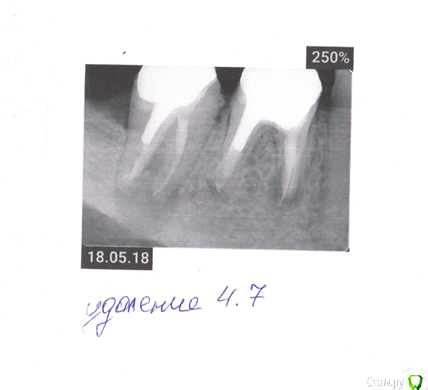

Andre5891 Опубликовано 22 мая, 2018 Поделиться Опубликовано 22 мая, 2018 Добрый день! Подскажите, пожалуйста, по снимкам.7-ка на удаления. Вопрос в том, какую имплантацию делать: одноэтапную или двухэтапную. У разных врачей разное мнение. По ссылке в теме "Ликбез" - я понял, что тут одноэтапную никак? По 6-ке - пытаться лечить или сразу на имплантацию? пс. 7-ка терпит еще 2 недели или тут лучше максимально быстро на удаление. Ссылка на комментарий

red_butler Опубликовано 23 мая, 2018 Поделиться Опубликовано 23 мая, 2018 Отсроченная имплантация 1 Ссылка на комментарий

Bier Опубликовано 23 мая, 2018 Поделиться Опубликовано 23 мая, 2018 согласен, тут нужно отсрочено делать если 6ка, не стадия заживления, то тоже на удаление скорее всего Ссылка на комментарий

red_butler Опубликовано 23 мая, 2018 Поделиться Опубликовано 23 мая, 2018 если 6ка, не стадия заживления, то тоже на удаление скорее всего +1, шестой кандидат на удаление Ссылка на комментарий